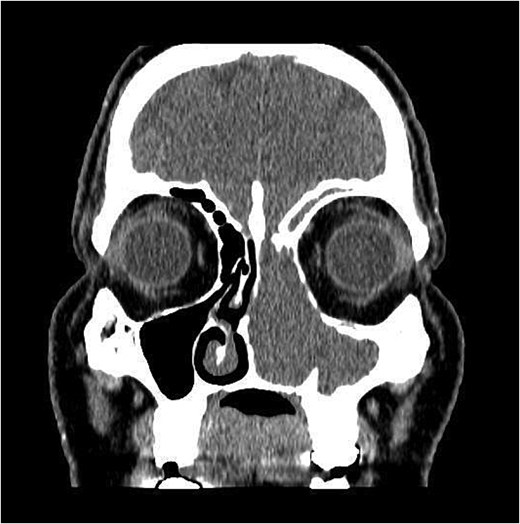

The patient underwent staging CT which was negative for distant metastasis. He then went underwent incomplete medial maxillectomy, ethmoidectomy, and sphenoidotomy followed by 10 sessions of immunotherapy abroad. He presented to our institution for follow up 6 months later with history of left nasal block and epistaxis. Nasal flexible scope showed a reddish nasal mass with greenish secretions (Fig. 3). Follow up CT revealed tumor recurrence (Figs 4 and 5). He was advised for multidisciplinary team evaluation to plan the treatment but he refused any intervention and lost follow up.

Coronal section of CT paranasal sinus bone window showing bony erosions of nasal septum, maxillary wall, lamina papyracea, and cribriform plate.